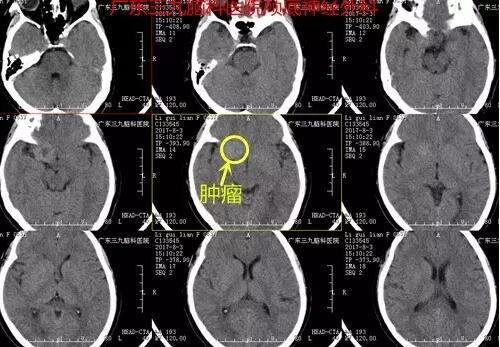

神经外科张良主任接待力李女士。在详细了解病情后,医生建议她先做头部检查,待结果回报后再做判断。结果显示:右侧鞍旁偏上方团块状占位。通过检查结果及之前李女士自己叙述的病症情况,确诊为颅内占位。

图1:术前CT提示右侧鞍旁蝶骨嵴内侧类圆形稍高密度影

图2:术前磁共振示右侧鞍旁偏上方团块状占位,呈长T1长T2,增强后明显异常强化,中心少许无强化区,大小约2.6cm×2.6cm×2.7cm

图3:CTA提示邻近右侧大脑中动脉M1段明显受压呈弧形改变